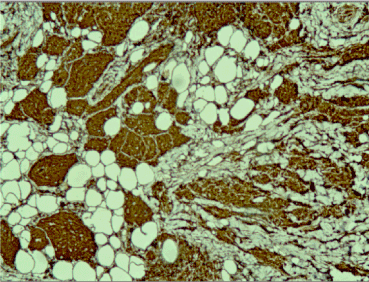

A frozen section was performed during surgery and the result was “invasive tumor, suspicious for malignancy”. Radical left mastectomy was performed with axillary lymph nodes dissection. The histological examination of the symptomatic lesion (11 mm) revealed a tumor, composed of nests of epitheloid tumor cells with monomorphous nuclei with occasional nucleoli, areas with spindle tumor cells in a fibrous background with hyaline change, areas with mature adipocytes. Peripheral nerves were surrounded by tumor nests (Figure 1). Scattered lymphocytic infiltrates were also found. PAS reaction revealed single positive granules in a few tumor cells (Figure 2). The described histological findings are observed in both mammary MFB and granular cell myoblastoma. Immunohistochemical analysis was performed. The tumor cells were positive for: S-100 protein (Figure 3), CD68 (Figure 4), Vimentin (Figure 5). The proliferative index detected with Ki67 is low (1-2%) (Figure 6). The tumor cells were negative for ER, PR and HER. The histological examination of the dissected lymph nodes revealed sinus histiocytosis, follicular hyperplasia and lipomatosis. Metastases were not found.

Lipomatous MFB is composed of mature monotonous adipocytes that lack nuclear pleomorphism. The cellular areas in the tumor include spindle and oval-shaped cells with morphological and immunohistochemical features typical for classic MFB. Lipomatous MFB should be differentiated from other benign lesions, like fibromatosis, nodular fasciitis and spindle cell lipoma, as well as from malignant spindle cell tumors, like spindle cell liposarcoma, malignant spindle cell myoepithelioma, low grade fibrosarcoma/malignant fibrous histiocytoma [11].

Figure 2. PAS reaction revealed single positive granules in a few tumor cells x40